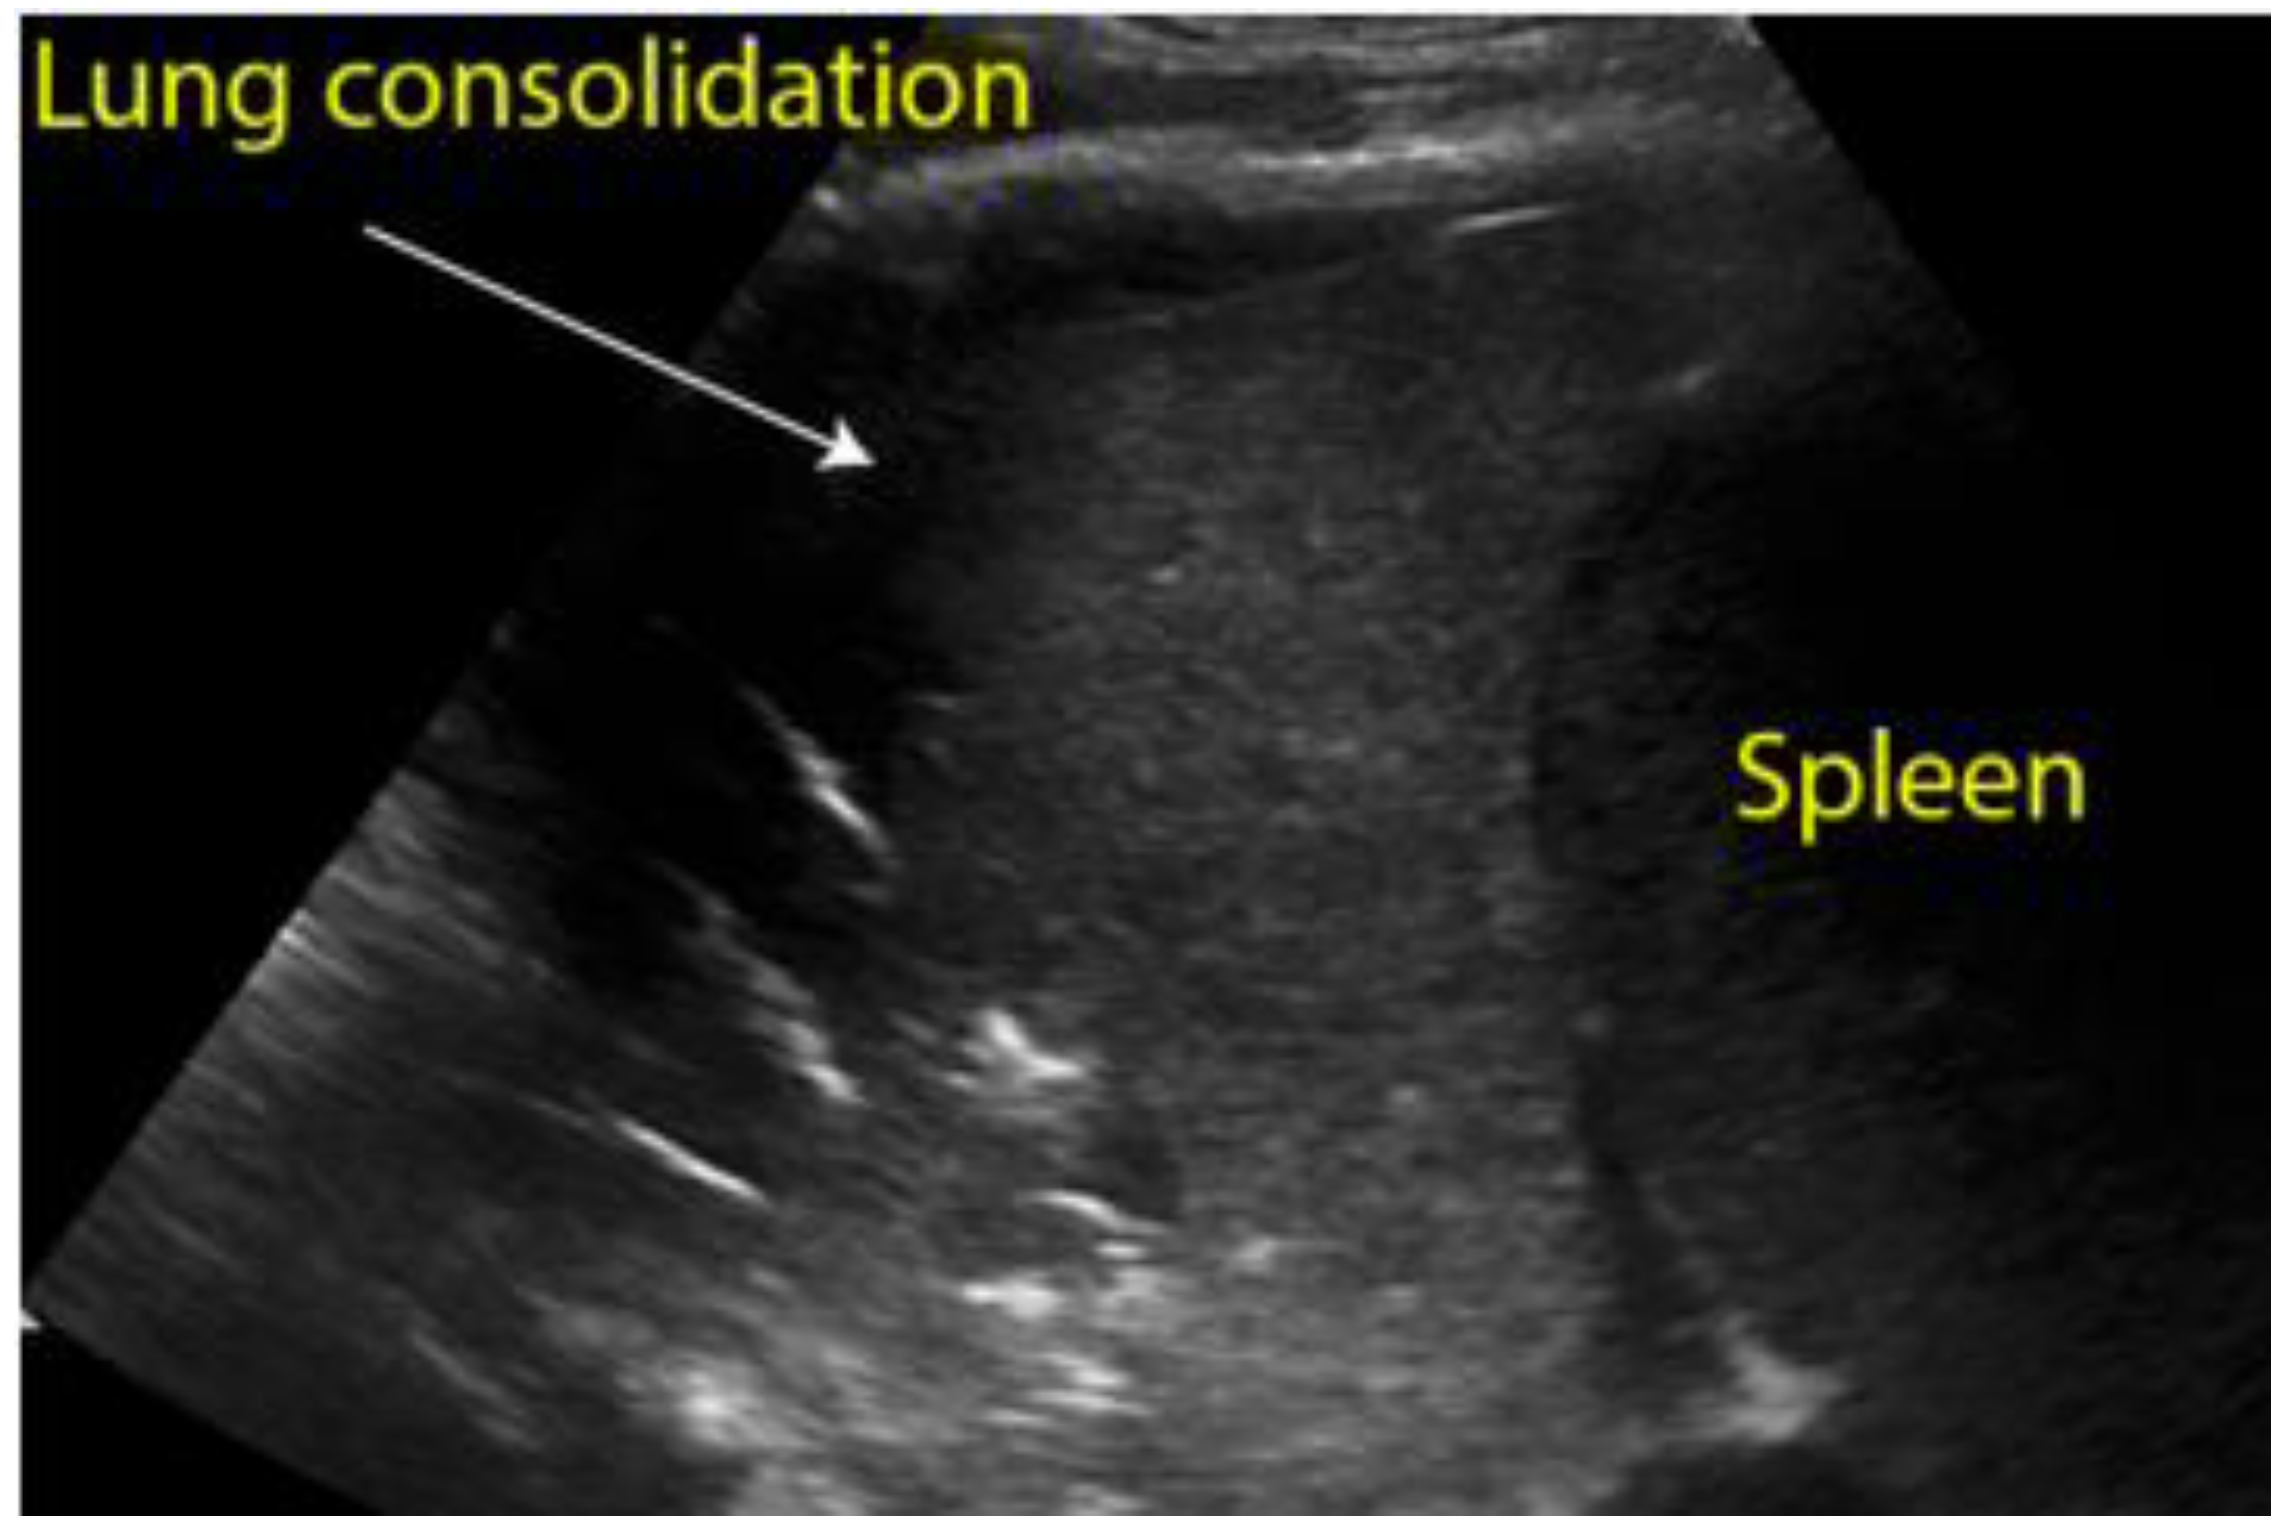

| Pneumonia | Consolidation, air bronchogram sign (Figure 8) |